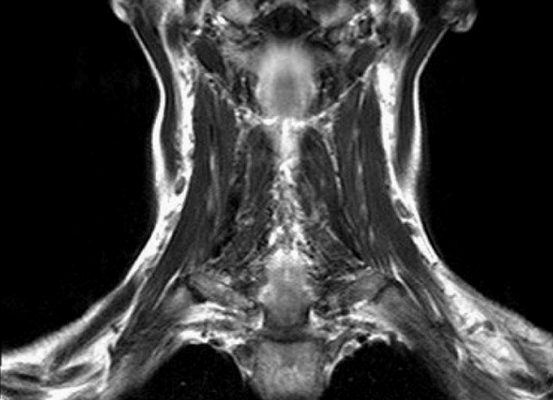

Результат МР-сканирования мягких тканей шеи

МРТ мягких тканей шеи назначают при наличии следующих симптомов:

дисфункция слюнных желез;

нарушения мозгового кровообращения;

признаки заболеваний щитовидной железы;

гипертония неясной этиологии и пр.

В этом случае врач назначает в качестве метода диагностического исследования магнитно-резонансную томографию. Применение магнитного поля безопасно для организма и дает возможность детально рассмотреть на послойных снимках структуру мышечной и жировой ткани, особенности строения слизистой, визуализирует состояние щитовидной железы, лимфатических узлов.

При исследовании шеи особое значение имеет сканирование гортани. Это сложный орган, в состав которого входят костные и хрящевые элементы, мышечная ткань, связочный аппарат. Частая локализация опухолей в области гортани является одной из причин тщательного обследования данной зоны.

МРТ информативнее при изучении состояния связок и мышц органа, выявляет

патологические процессы (воспалительные, неопластические), определяет локализацию поражения.